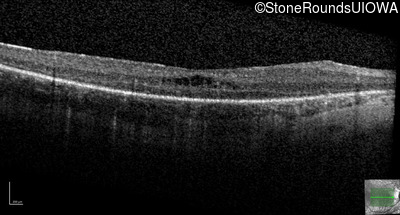

Optical Coherence Tomography - Left - 20/100 sc

Exemplar / OCT Stack